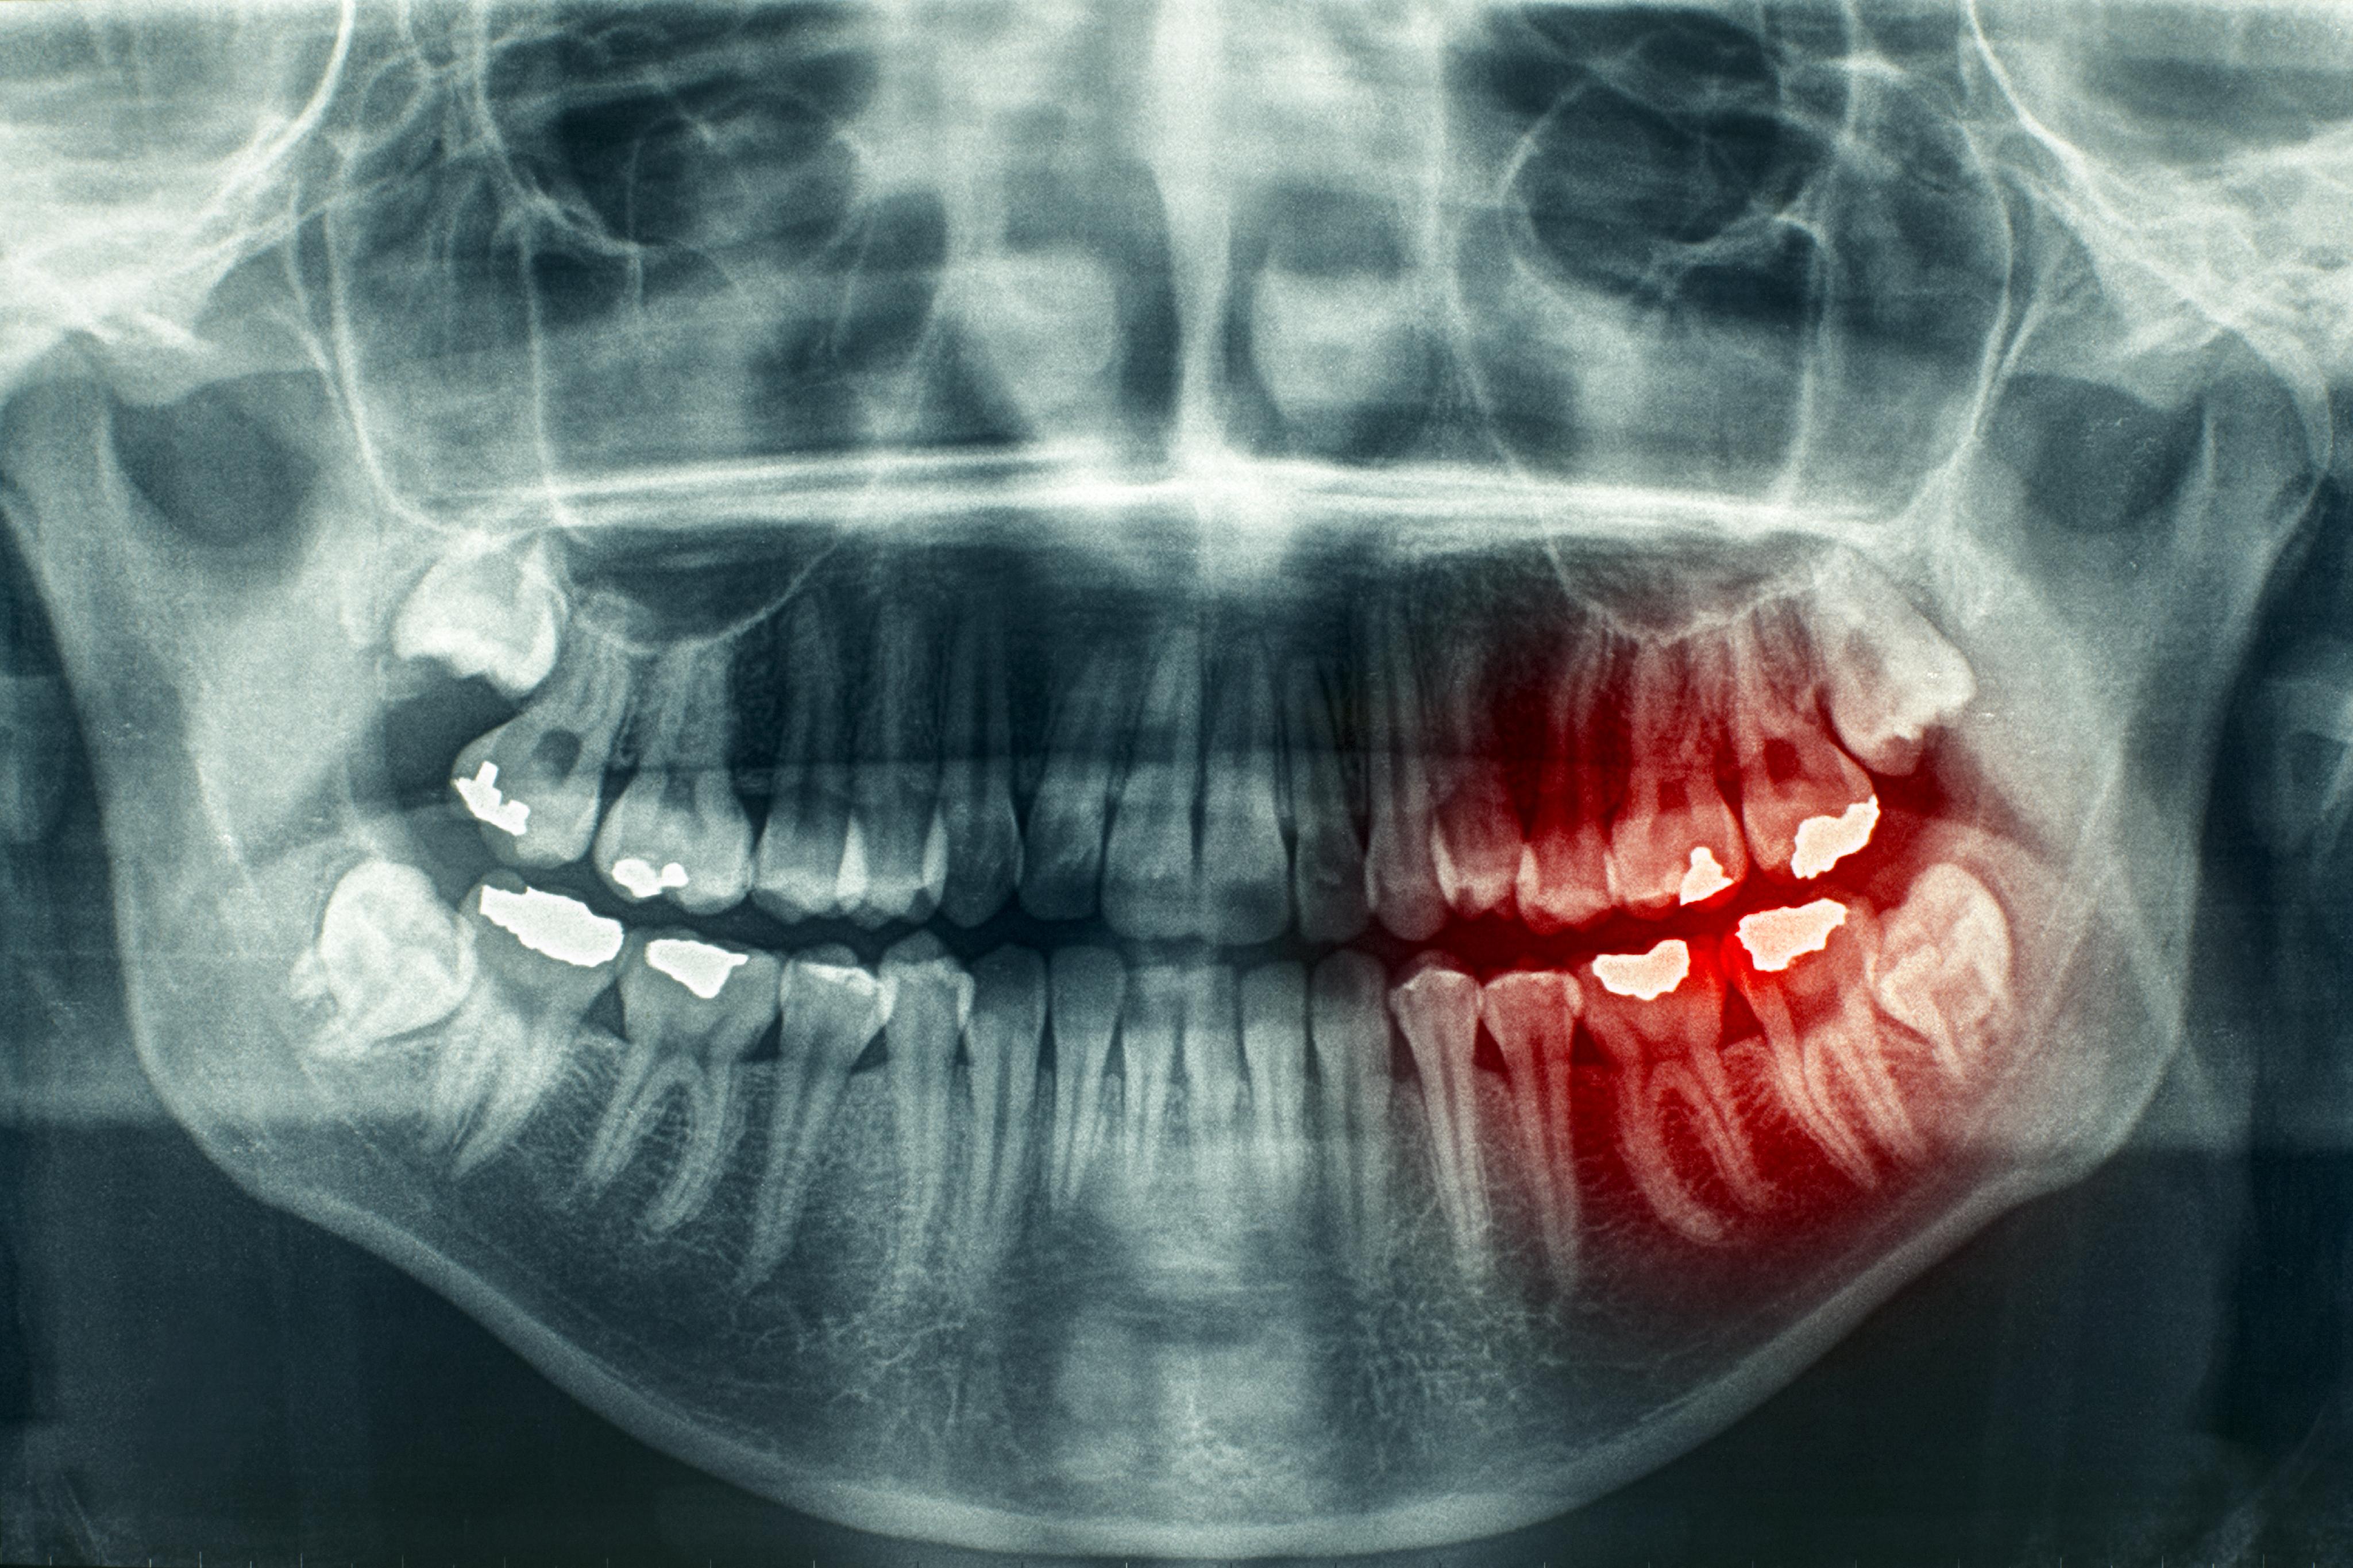

Cancer Treatment Dental Problems . These drugs kill cancer cells, but they may also harm normal cells, including cells in the mouth. The national cancer institute (nci) recommends that dental professionals be considered part of the cancer care team in. Cancer patients have a high risk of oral complications. If dental problems are treated before cancer treatments begin, there may be fewer or milder oral complications. Chemotherapy, targeted drugs, immunotherapy and radiotherapy work by killing cancer cells or stopping them from. Many cancer treatments, including chemotherapy and radiat. The national cancer institute recommends that you see the dentist 4 weeks before you begin chemotherapy or radiation. So the question arises, how can we, as dental health professionals, best look after and advise these patients before, during and after. Oral complications of cancer treatment arise in various forms and degrees of severity, depending on the individual and the cancer treatment. Chemotherapy is the use of drugs to treat cancer.